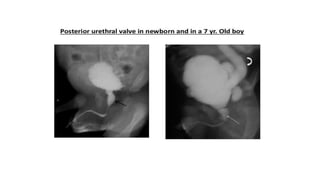

8. Boys with hematuria-MCU can demonstrate posterior uretheral valve or polyp.

INDICATIONS Children: 1. UTI 2. Voidingdifficulties like dysuria, thin stream, dribbling, frequency, urgency. 3. Vesico ureteric reflux. 4. Other congenital anomalies : Meningomyelocele, Sacral agenesis,Rectal anomalies. 5. For post operative evaluation of ureteric abnormalities. 6. Pelvic Trauma. 7. In renal failure to exclude reflux. 8. Boys with hematuria-MCU can demonstrate posterior uretheral valve or polyp.